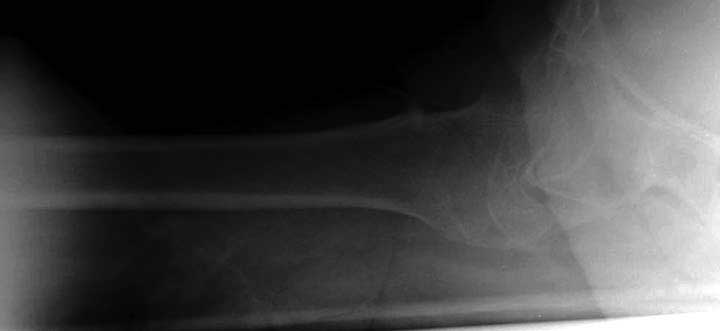

Первые снимки показывают технические погрешности установки DHS. Не была достигнута репозиция, конечность в флексии и шейка в ротации. Сегодня все меньше обращают внимание на параметры для оценки репозиции (S контуры Lowell в обеих проекциях и Garden Alignment Index, в норме 155 и 180 градусов), хотя такие простые тесты помогли бы дорепонировать смещение. Винт находится сзади в головке, что при нагрузке поменяет вектор и вместо компрессии в линии перелома срежет головку-Cut Out!

В зависимости от дистанции линии перелома и латерального кортекса надо использовать разной длины barrel, т.е. конец баррели не должен доходить до пределов перелома. Здесь конец длинного ствола упирается в медиальный фрагмент, что мешает созданию компрессии, а более короткий barrel создал бы запас для компрессии. В боковой пластине вместо 4х можно было ограничится двумя шурупами, потому что головка шурупа в 4.5 мм выдерживает давление до 350 кг.